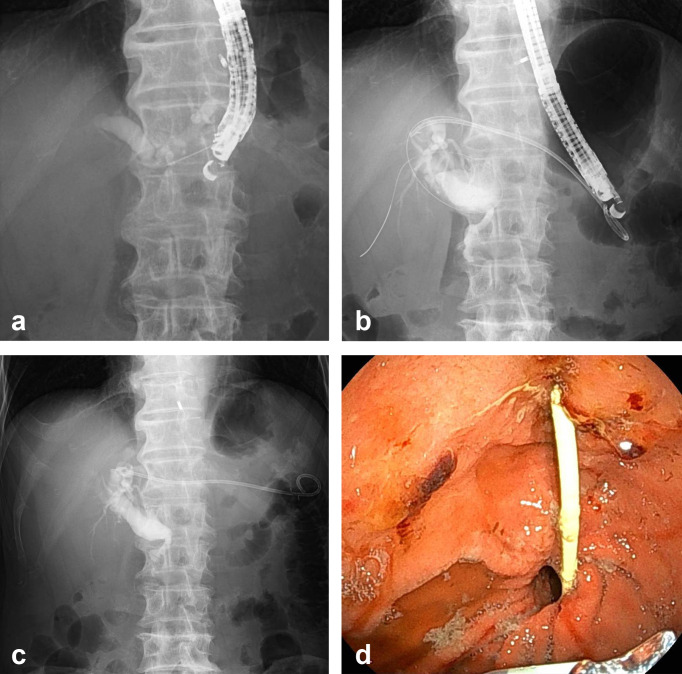

Objective: We report a case of spontaneous migration of a dedicated plastic stent after endoscopic ultrasound-guided hepaticogastrostomy (EUS-HGS) in a patient with surgically altered anatomy. Patient: The patient was a male in his 70s. He underwent EUS-HGS with the successful insertion of a dedicated plastic stent and had no obvious postprocedural complications. However, nine days after the procedure, the patient visited our hospital because of abdominal pain, fever, and stent excretion. We performed EUS-HGS with antegrade stenting, after which the patient had no further complications. Conclusion: Stent migration is considered a complication requiring caution when performing EUS-HGS in patients with surgically altered anatomy.